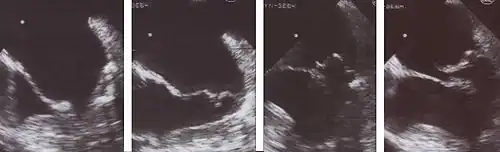

Animation of a mitral valve regurgitation in a dog, left apical view

An echocardiogram is commonly used to confirm the diagnosis of MR.[16] Color doppler flow on the transthoracic echocardiogram (TTE) will reveal a jet of blood flowing from the left ventricle into the left atrium during ventricular systole. Also, it may detect a dilated left atrium and ventricle and decreased left ventricular function.[6] A transesophageal echocardiogram can give clearer images if needed as the back of the heart can also be viewed.[17]